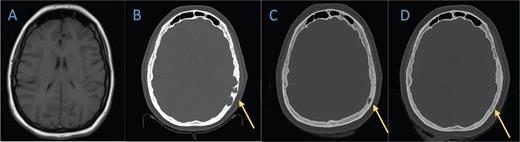

Coronal computed tomography (CT) head bone window demonstrates lytic lesion along the frontal cranium near the vertex which is not evident on the A) brain MRI from 2019. B-D) Subsequent head CTs obtained nine months later show significant interval decrease in size of the lytic lesions. Follow-up head CT in eight months demonstrates further evidence of healing.